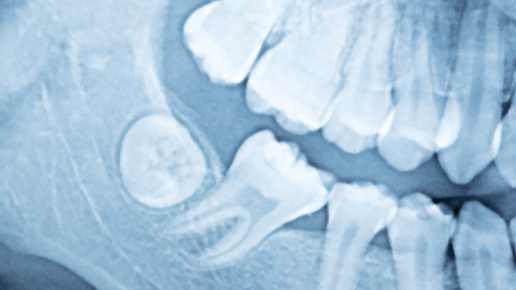

Название зубов мудрости даже звучит загадочно. Неудивительно, что у пациентов по ним — масса вопросов. Попросили ответить на них нашего стоматолога-хирурга Игоря Юрьевича Малиновского. Вообще, зачатки зубов мудрости закладываются в челюсти в раннем детстве. Если взглянуть на рентгеновский снимок ребенка 8-10 лет, то можно увидеть, что изначально «восьмерки» представляют собой маленькие шарики. Примерно к 12 годам у шариков формируется коронковая часть, а в 15-17 лет начинают удлиняться корни. Корни продолжают расти до 21-22 лет, в редких случаях — до 27 лет...